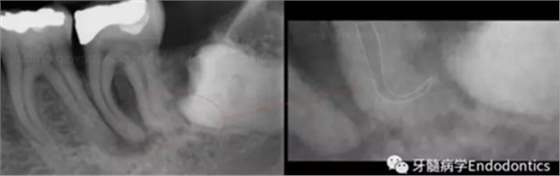

圖2.疏通根管冠方2/3后,使用次氯酸鈉溶液沖洗根管,且可以使用手用器械、GG鉆(刷洗動作)、旋轉(zhuǎn)鎳鈦成形銼預(yù)敞根管。當(dāng)冠方2/3進(jìn)行了合適的預(yù)備且充滿沖洗液后,接著進(jìn)行根尖1/3的探查以收集信息。使用小的手用銼(8號或10號K銼)疏通根管的剩余部分,確認(rèn)建立了流暢的、無阻礙的、平滑的到達(dá)根尖止點(diǎn)的引導(dǎo)通道。

圖3.存在細(xì)小狹長、可能多維的復(fù)雜根管解剖時(shí),使用10號K銼不可能立即疏通根管到達(dá)根尖止點(diǎn)。隨后醫(yī)生應(yīng)嘗試使用更小的銼探查以達(dá)到根尖。但是,通常不需要使用6號和8號K銼對到達(dá)根尖的引導(dǎo)通道進(jìn)行擴(kuò)大,除非是特別困難的病例。